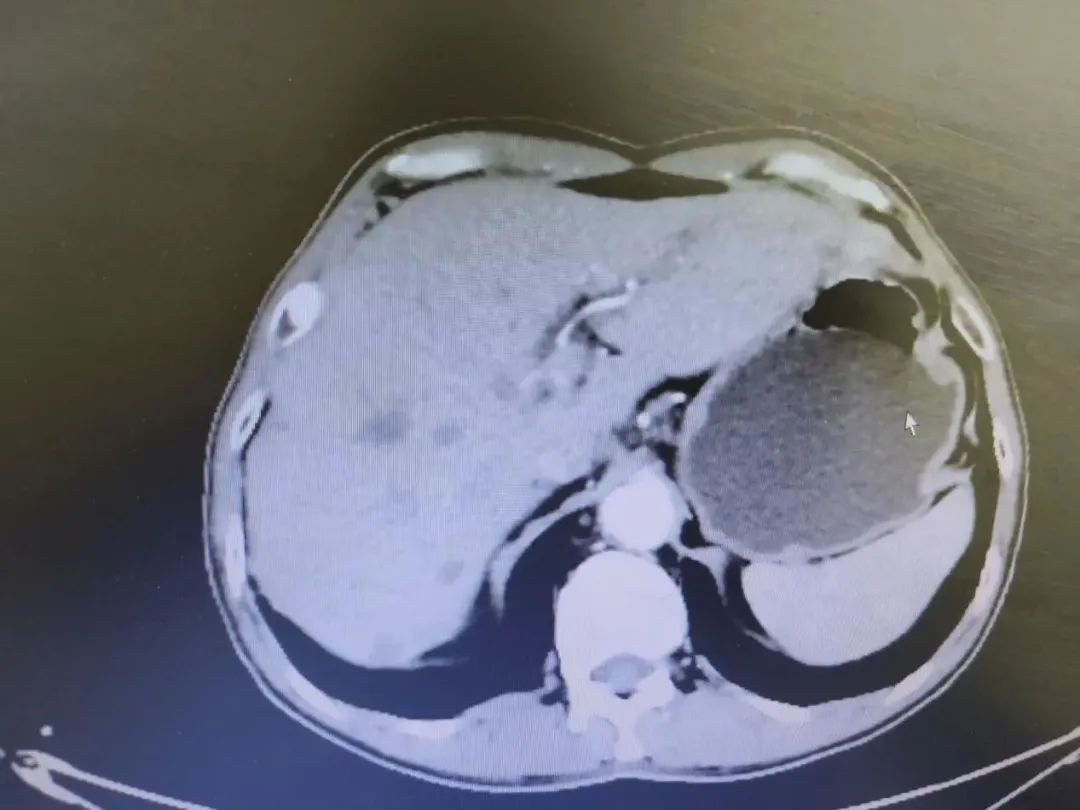

我院4周期化疗后影像(2022年5月1日)